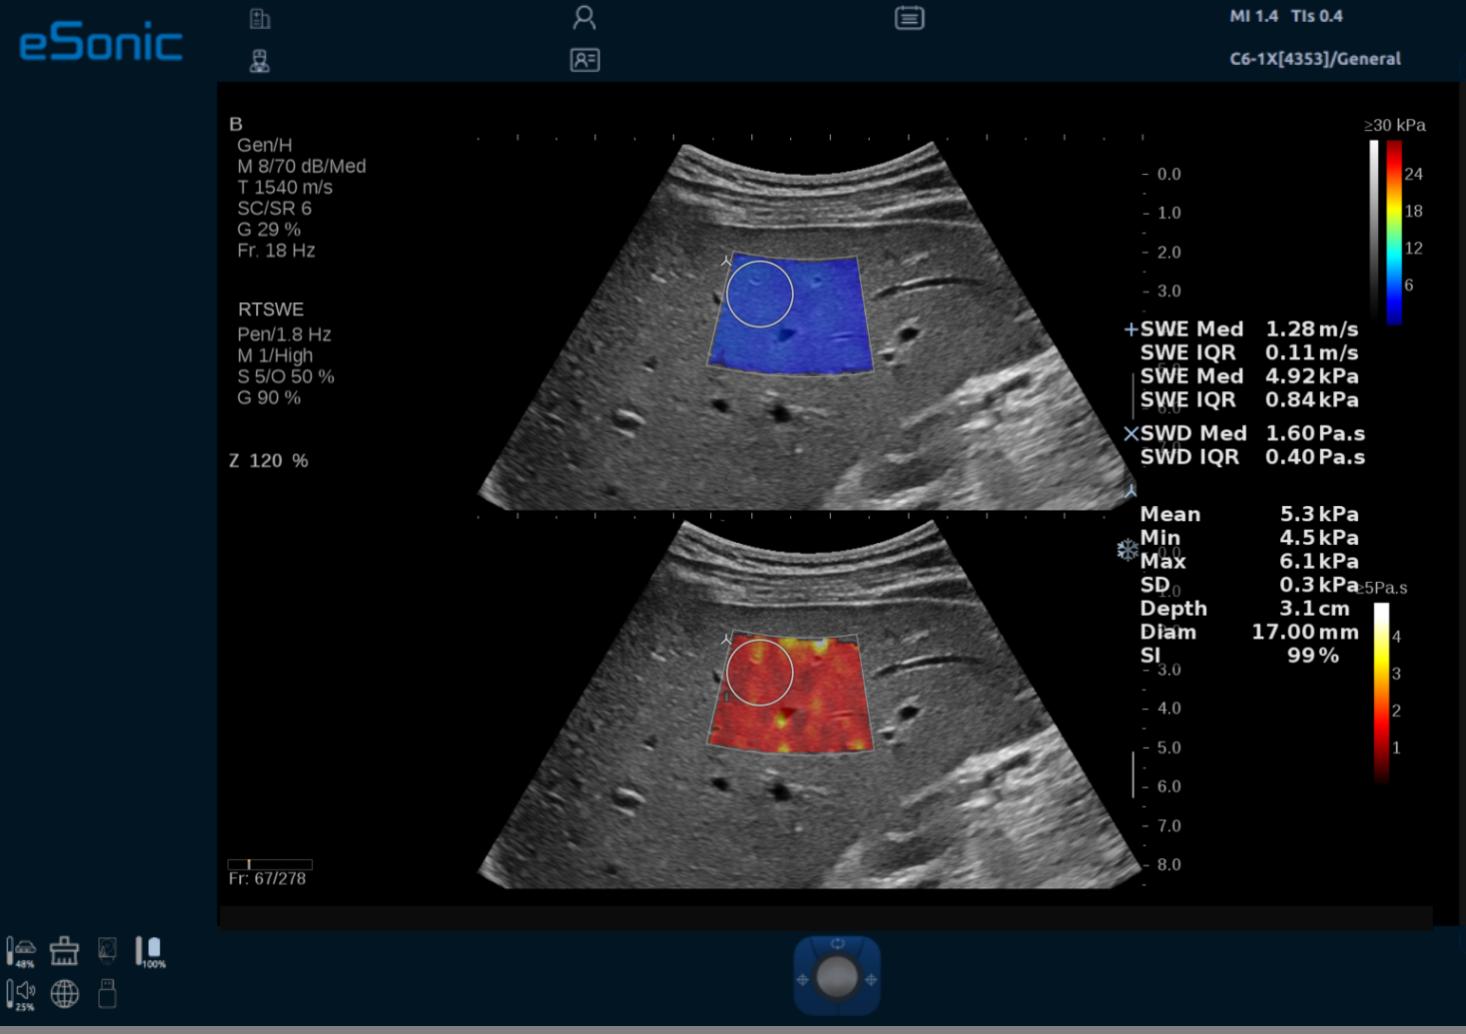

3D RTSWE 三维剪切波硬度定量成像

QVisco 粘弹性定量成像